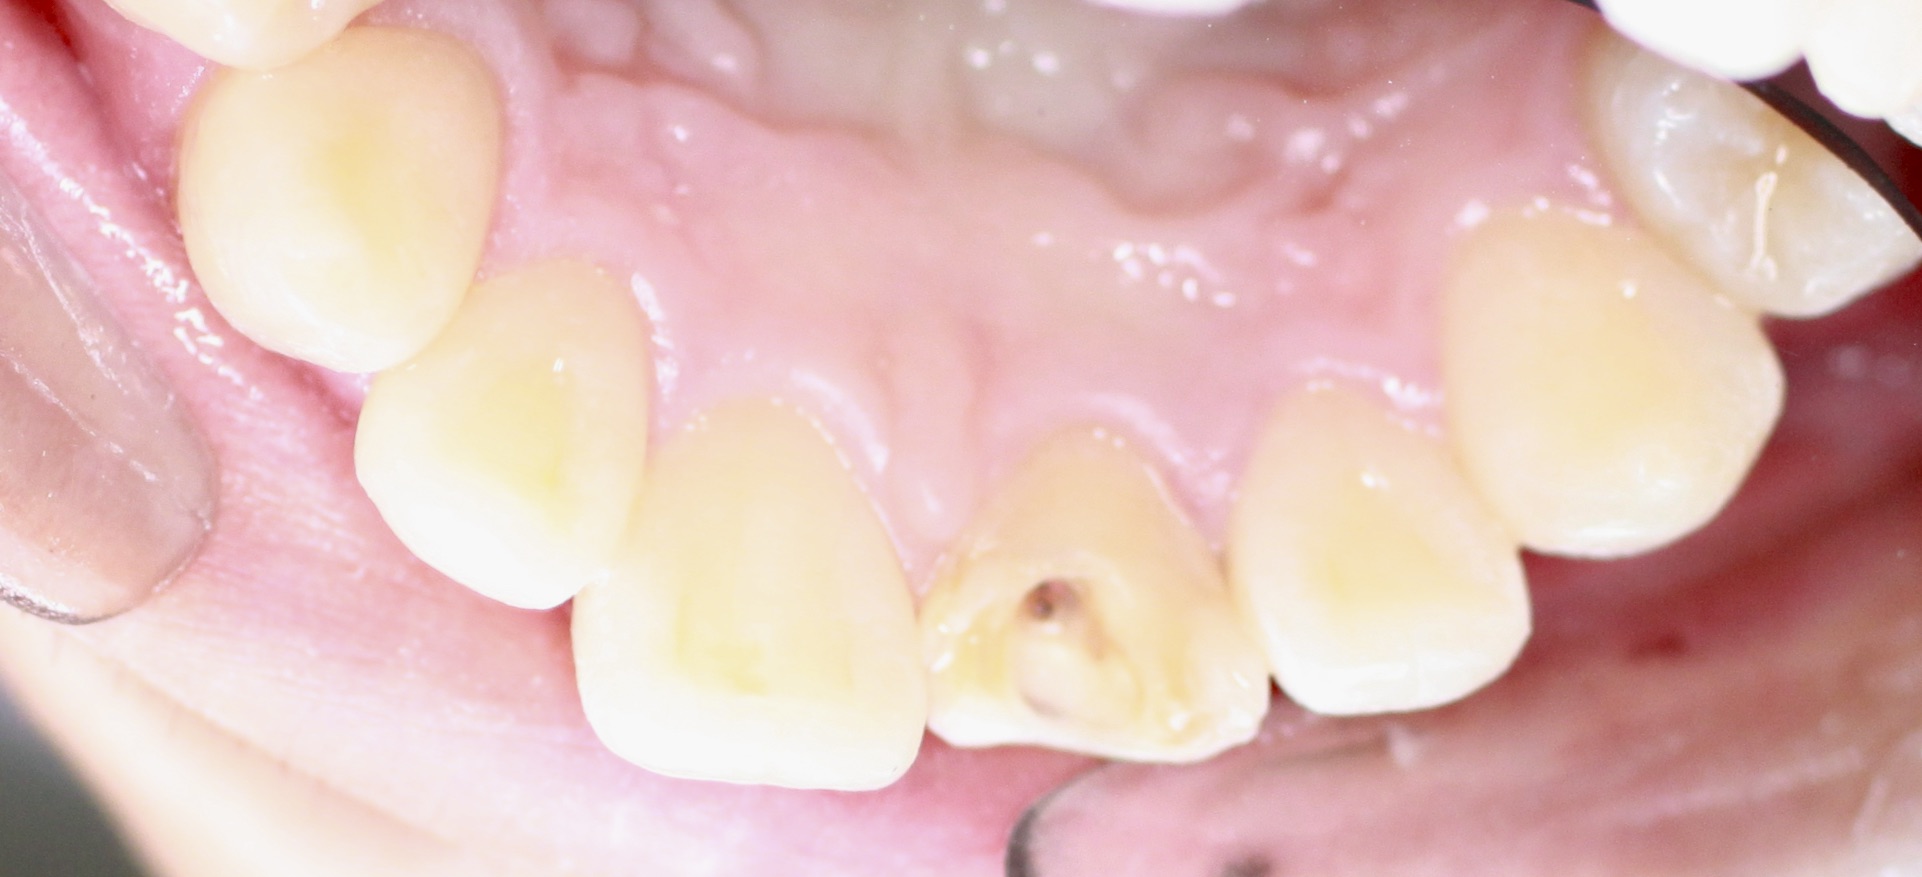

Gallery